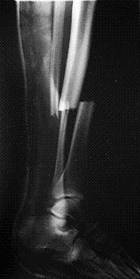

A 74-year-old woman with osteoporosis, polymyalgia Rheumatica and COAD suffered a spiral fracture of the distal femoral diaphysis (AO 32 B1). The fracture (Fig. 8.a&b) was treated by open reduction and stabilisation with a 15-hole LCP Distal Femur Plate (Fig. 8.c&d) using 13 looked screws (one hole in the shaft portion of the plate at the fracture site and one hole in the head of the plate were left unoccupied).

e. f. g.

Figure 8. Clinical case of a femoral fracture in a 74 year old patient treated with a LCP. The preoperative (a&b), post operative (c&d), implant failure at 22weeks (e&f) and follow up radiographs one year after IM nailing (g) are shown.

Follow-up radiographs after 22 weeks (Fig. 8.e&f) revealed plate breakage at the middle part of the original fracture. No callus formation was visible at the level of the fracture. She then underwent IM nailing of her right femur and subsequent radiography after 1 year revealed complete consolidation with marked callus formation (Fig. 8.g).